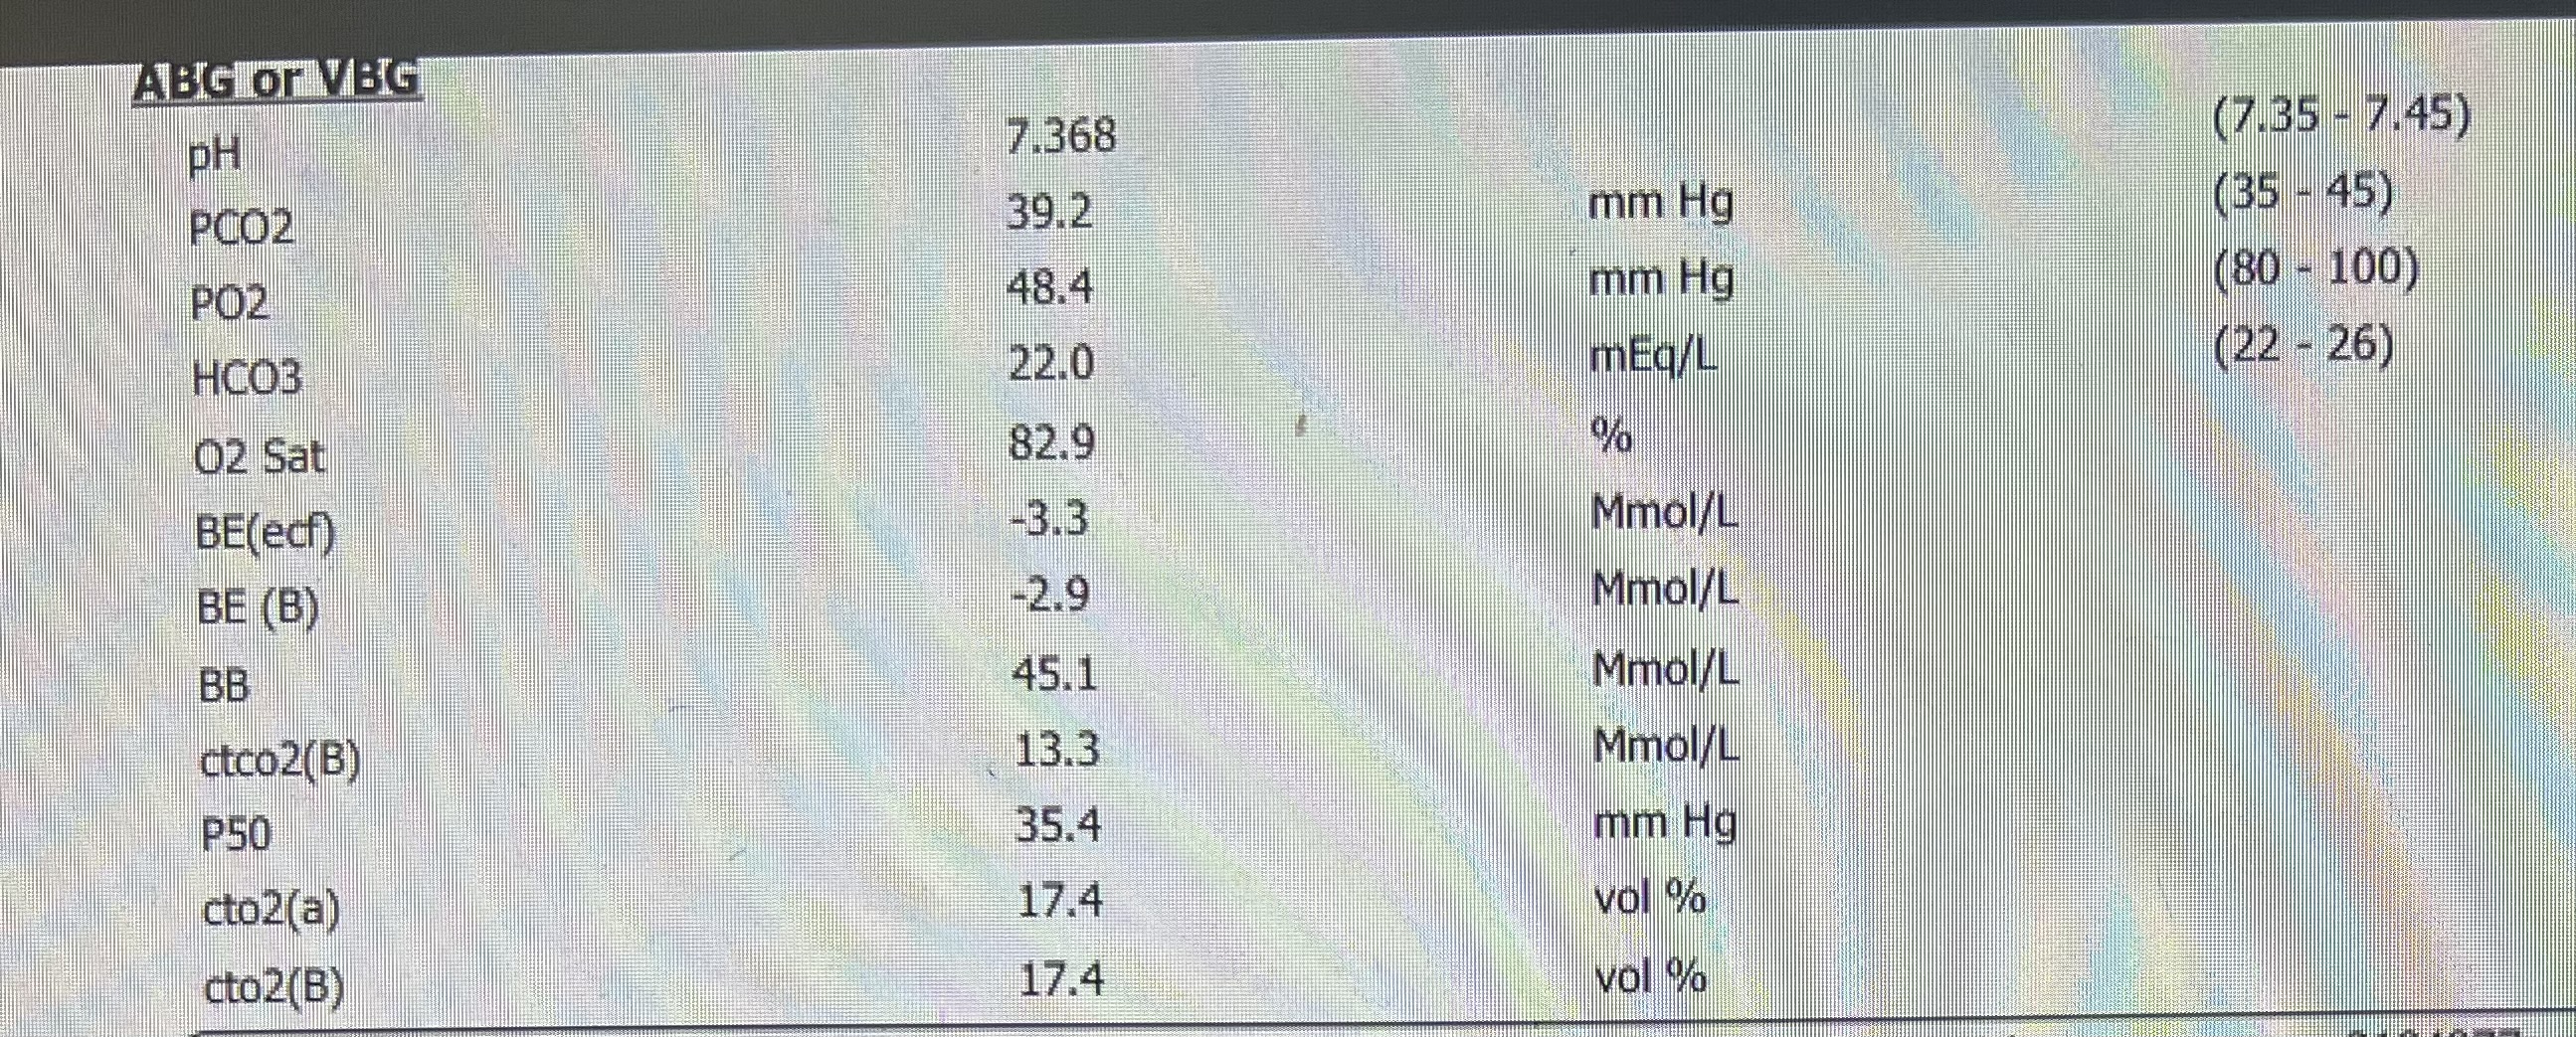

VBG